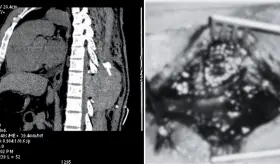

El antecedente de fracturas costales recurrentes por tos y el uso prolongado de omeprazol, un inhibidor de la bomba de protones, son factores que contribuyen a la disminución de la densidad ósea, favoreciendo la osteoporosis.